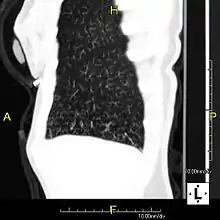

| Sagittal reformatted CT image showing "tree in bud" appearance of impacted distal small airways in primary ciliary dyskinesia | |

In radiology, the tree-in-bud sign is a finding on a CT scan that indicates some degree of airway obstruction.[1] The tree-in-bud sign is a nonspecific imaging finding that implies impaction within bronchioles, the smallest airway passages in the lung. The differential for this finding includes malignant and inflammatory etiologies, either infectious or sterile. This includes fungal infections, mycobacterial infections such as tuberculosis or mycobacterium avium intracellulare, bronchopneumonia, chronic aspiration pneumonia, cystic fibrosis or cellular impaction from bronchovascular spread of malignancy, as can occur with breast cancer, leukemia or lymphoma.[2] It also includes lung manifestations of autoimmune diseases such as Sjögren syndrome or rheumatoid arthritis.[3][4]

Histopathologic studies have shown that the tree-in-bud pattern is caused by demarcation of the normally invisible branching course of the peripheral airways, which usually results from bronchioles being plugged or blocked with mucus, pus or fluid. In addition, dilated and thickened walls of the peripheral airways and peribronchitis can make the affected bronchioles more easily visible, as is seen in patients with cystic fibrosis.